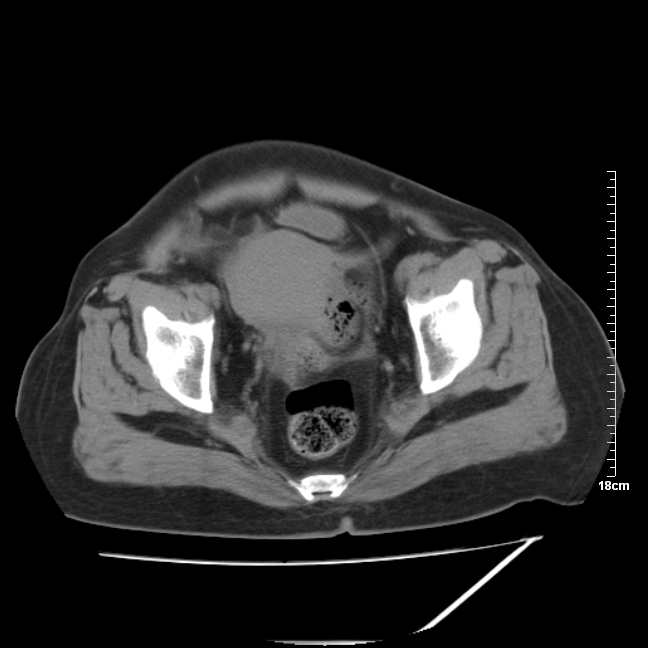

以下是引用jinning在2007-5-17 11:18:00的发言:[br]考虑右侧卵巢囊腺瘤合并少量出血可能性大